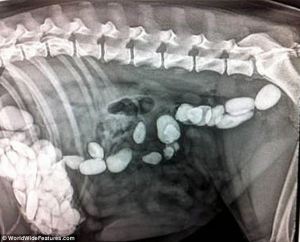

Ele comeu 109 pedrinhas durante um passeio na praia, segundo reportagem do jornal “Daily Mail”. A dona Kim Woollard, de 52 anos, que mora em Chessington, no Reino Unido , levou o labrador ao veterinário depois que o animal passou mal. Após realizar um Raio-X no animal, foram encontradas 79 pedras no seu estômago.

E quando chegaram em casa a sua dona encontrou mais 30 na sua caminha, que já tinha passado pela digestão.